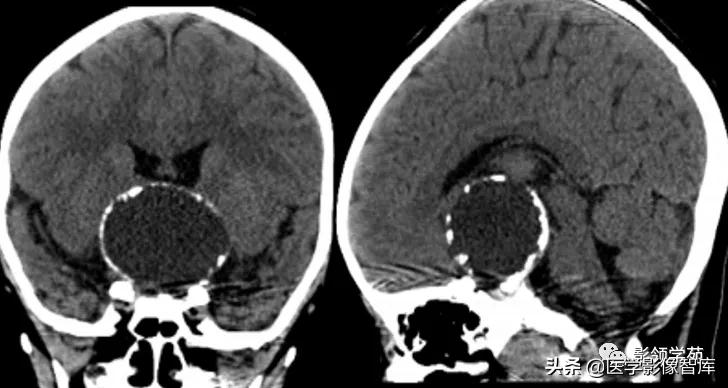

女 61岁 反复头晕3年余

鞍上可见一类圆形均匀稍高密度灶,CT值约47HU,

边界清楚,其内见一小点片状钙化灶;继发鞍上池受压伴变性。

鞍区占位肿块,呈等T1等T2信号,信号均匀,边界清楚。

病灶呈均匀、显著强化(馒头样),以宽基底与前颅窝底相连,

冠状位和矢状位见脑(硬)膜尾征;

肿块突入鞍上池,向上推压视交叉,后缘紧邻垂体柄,与双侧颈内动脉相邻。